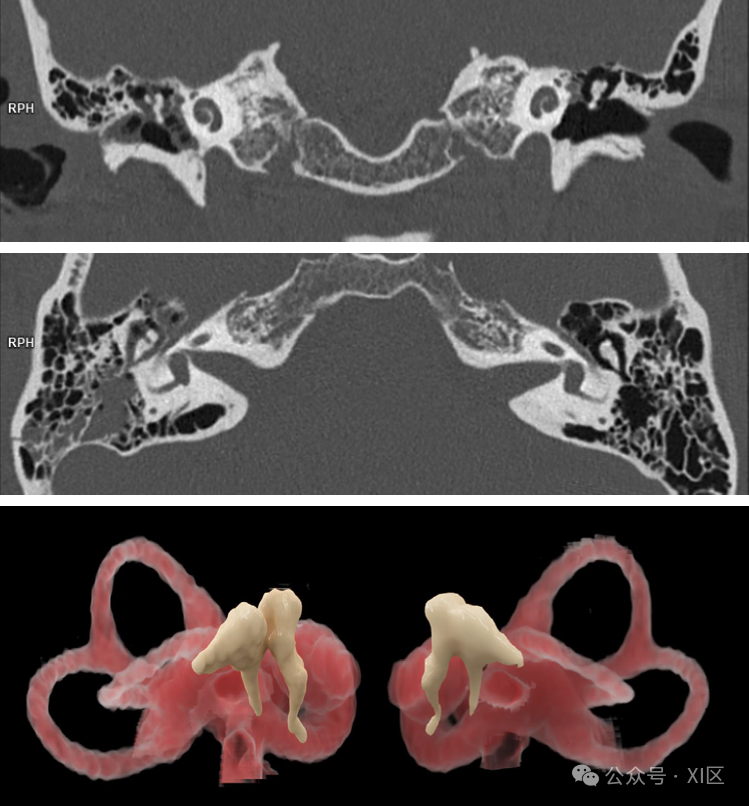

表现:空间分辨率可提升至传统CT的2倍以上。这意味着它能清晰显示以往不可见的微细结构,如微小血管、内耳细微结构以及骨小梁的微观架构。影像从“高清”进入了“超高清”时代。

患者女,33岁,外伤。到达时,意识不清,右耳有明显出血,颅骨右侧有表层血肿。使用光子计数探测器(PCD)CT扫描仪(NAEOTOM Alpha.Prime)对她进行常规头部CT扫描。图1:轴位图像(图1a)显示右侧锤骨头从砧骨体和短突处移位(箭头所示)。在冠状MPR图像(图1b)中可见典型的“心碎”征象(箭头所示)。用薄层(0.4毫米,Hr76的锐利内核)创建的两个cVRT图像(图1c和1d)以三维方式展示了砧骨锤骨脱位(图1c)。